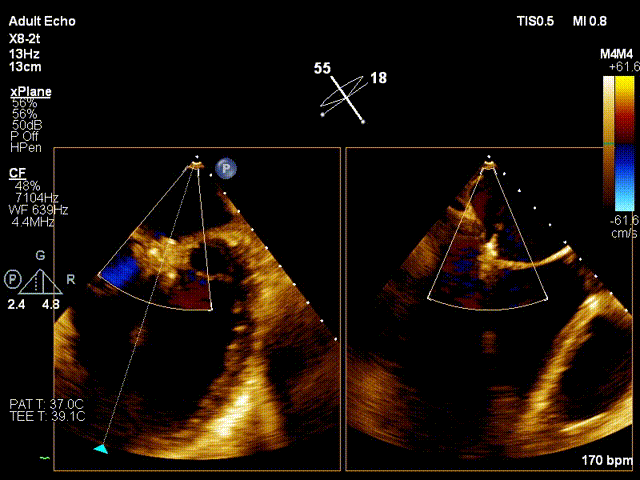

行TEE示:功能性重度二尖瓣反流、二尖瓣口舒张期几何面积 4.41cm²、收缩期二尖瓣口偏心性反流束缩流颈宽度7.2mm、PISA定量瓣口EROA=0.58cm²。STS评分高达22.1%。患者虽然为终末期心衰,二尖瓣反流量多,根据COAPT研究的结论, 患者具有TEER手术指征,考虑患者等待心脏移植一年,未有供体,但患者病情危重,心功能持续恶化,厦心结构性心脏病团队决定为患者实行经导管二尖瓣钳夹术。

之后迅速调整夹子位置,准确的捕获二尖瓣叶,完成了夹合。术后即刻(植入第一个夹子)TEE示:二尖瓣反流降低至中度,二尖瓣压差6mmHg;测定左房压力:23/20/17mmHg。

考虑患者残余反流仍偏高,经团队评估后,遂植入第二个夹子。术后即刻(植入第二个夹子)TEE示:二尖瓣反流降低至微量,二尖瓣压差1mmHg;测定左房压力:19/16/14mmHg,手术成功。患者术后即刻麻醉清醒,血压维持在110/60mmHg, 胸闷,呼吸困难症状明显缓解。

基线view

第一个架子后

Final